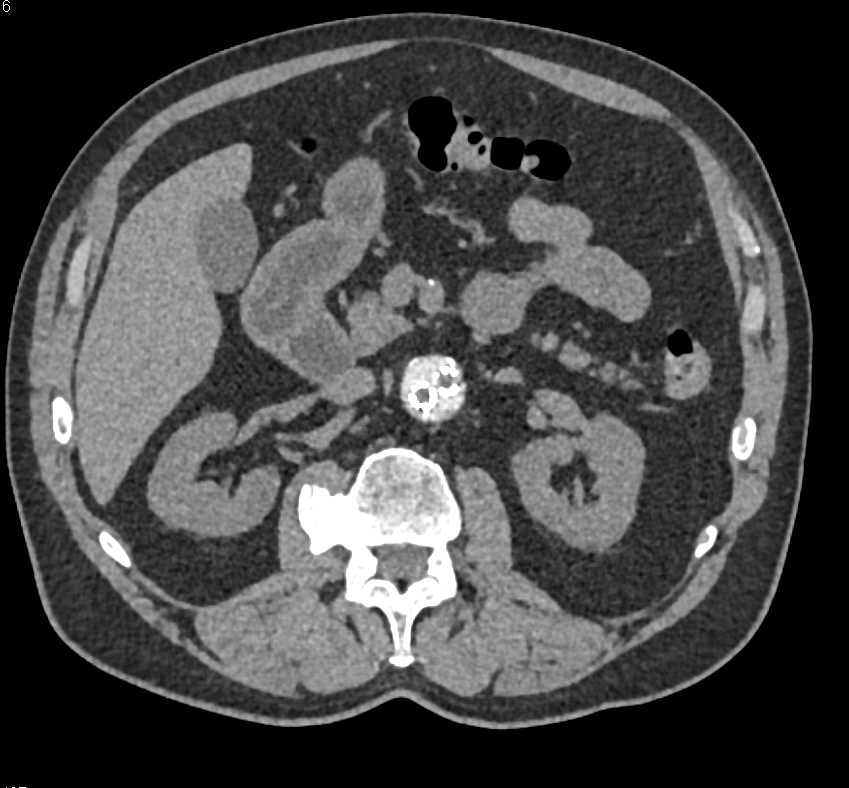

Renal Artery Pseudoaneurysm Near Partial Nephrectomy Site